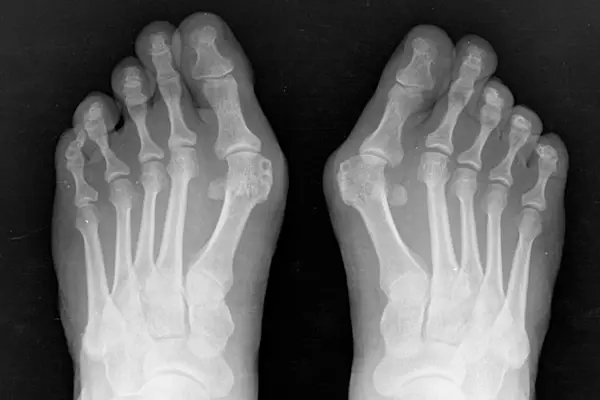

Key Highlights of Hallux Valgus (Bunion Surgery)

- Purpose: Correct deformity of the big toe, relieve pain, and restore foot alignment.

- When Recommended: For painful bunions, difficulty walking, or failure of non-surgical treatments.

- Procedure: Minimally invasive bunion surgery using small incisions and specialized instruments to realign the toe joint.

- Benefits: Less pain, minimal scarring, quicker recovery, and long-term correction.

- Success Rate: High — most patients achieve improved mobility, shoe comfort, and relief from chronic bunion pain.